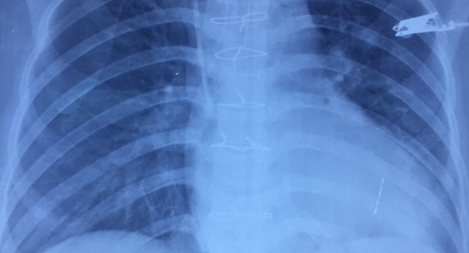

Ngày 10-12, Khoa Phẫu thuật Tim Mạch – Lồng ngực Bệnh viện Đa khoa Xuyên Á (BVXA) tiếp nhận bệnh nhân nữ tên: N.T.A. (35 tuổi, Huyện Đức Hòa, Tỉnh Long An) bị cướp tấn công gây một vết thương đâm thấu ngực, gây thủng tim, thủng cơ hoành, thủng gan và mạch máu trên gan đe dọa tính mạng trong gang tấc.